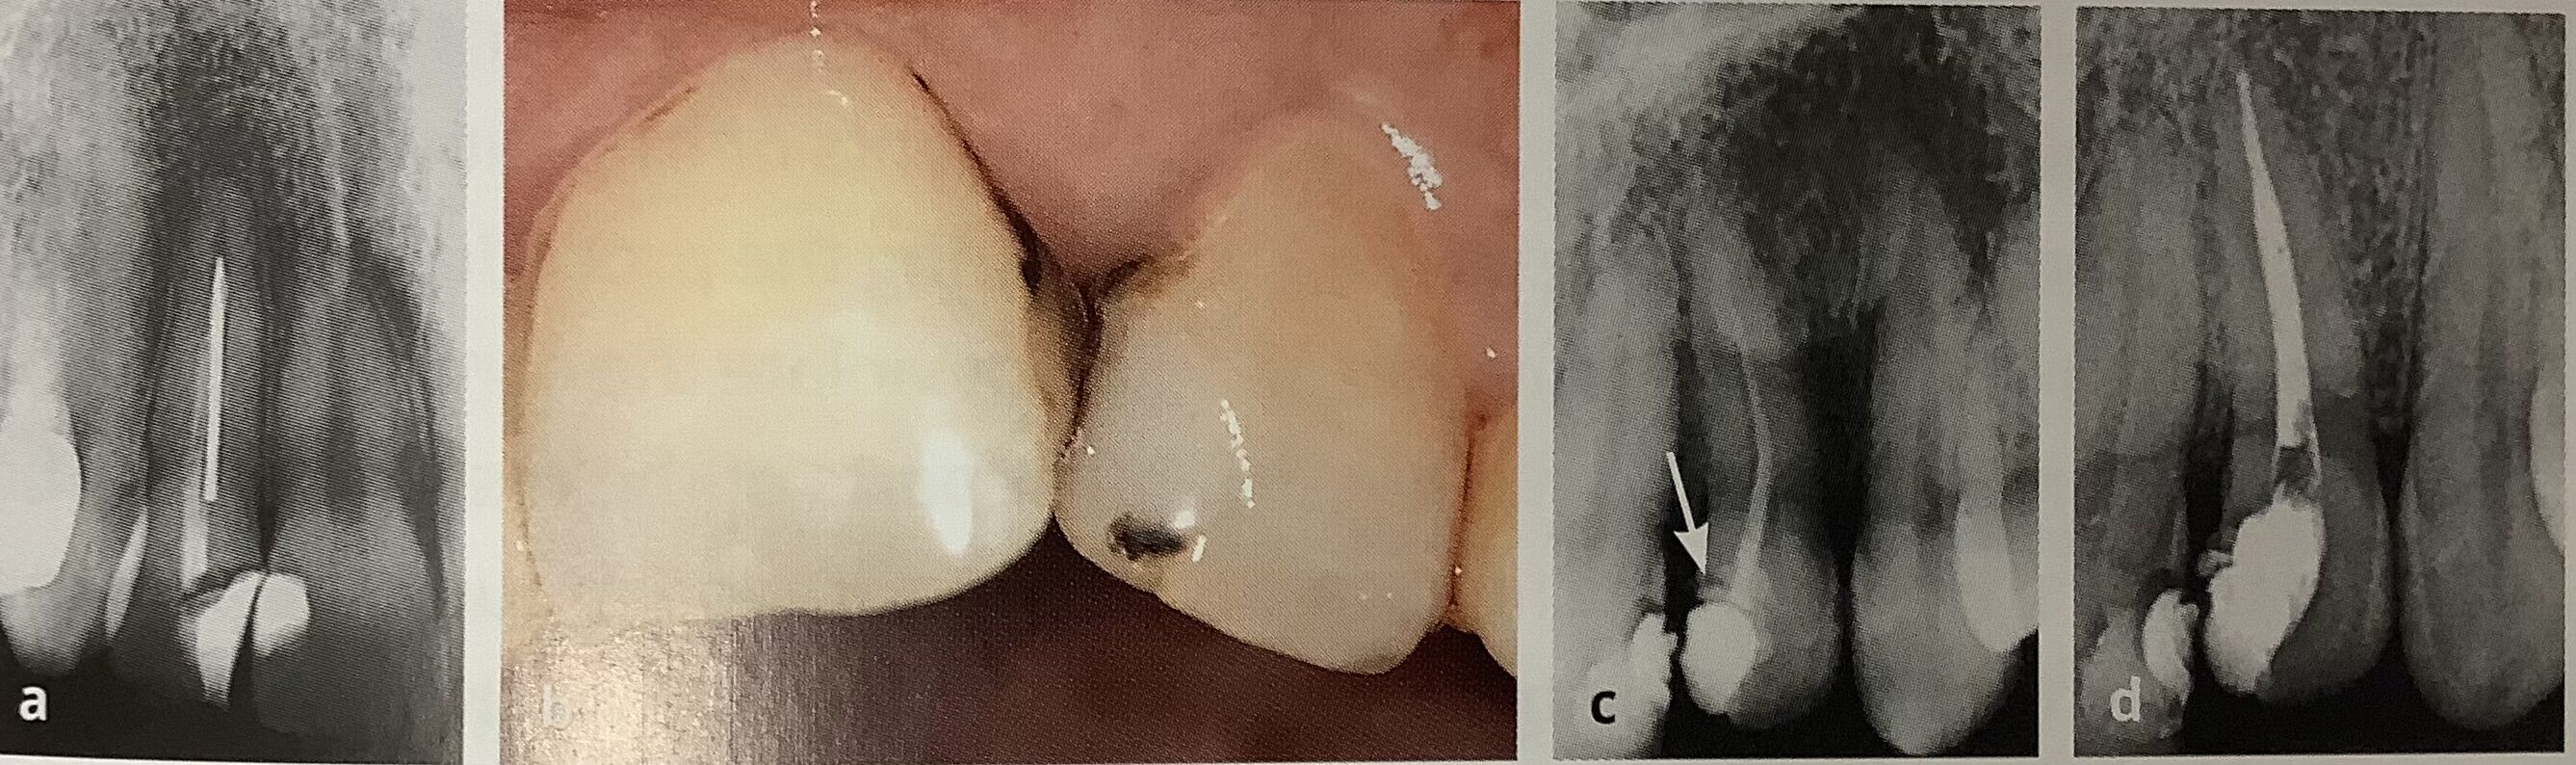

ÆÃ¤Ë¥Á¥¿¥óÀ½¤Ï¥ì¥ó¥È¥²¥ó¤Ç¥¬¥Ã¥¿¥Ñ¡¼¥Á¥ã¤ÈƱ¤¸¤Ë¸«¤¨¤Æ¡¢ÀÞ¤ì¤Æ¤ë¥Õ¥¡¥¤¥ë¤â¸«Ê¬¤±¤¬Æñ¤·¤¤¤Ç¤¹¡£

º¸¤Î¥ì¥ó¥È¥²¥ó¤Ç¿¿¤ÃÇò¤Ë¸«¤¨¤ëËÀ¤ß¤¿¤¤¤Ê¤Î¤¬¡¢Àޤ줿¥²¥¤¥Ä¤Î¥É¥ê¥ë¤Ç¤¹¡£

±¦¤«¤é2ÈÖÌܤΥì¥ó¥È¥²¥ó¤ÇÌð°õÉôʬ¤Î¶Ê¤¬¤ê¤¬¡¢¥¥Ä¥¤¤Ç¤¹¤Í¡£

¥Á¥ç¥Ã¥È¹¤²¤ë¤À¤±¤Ç¡¢±¦¤Î¤è¤¦¤Ë̵Íý¤Ê¤¯Àè¤Ã¤Ý¤Þ¤ÇÆÏ¤¯¤è¤¦¤Ë¤Ê¤ê¤Þ¤¹¡£